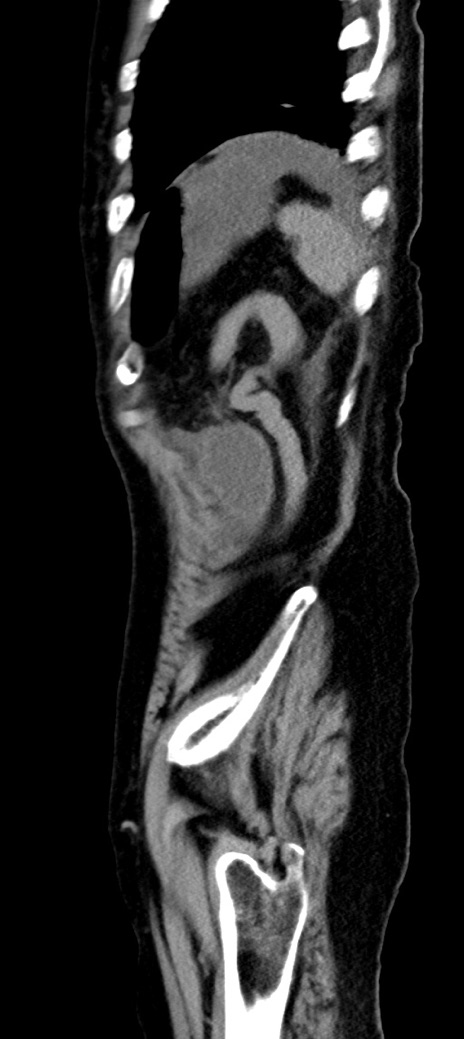

横断像

冠状断像

他院CT